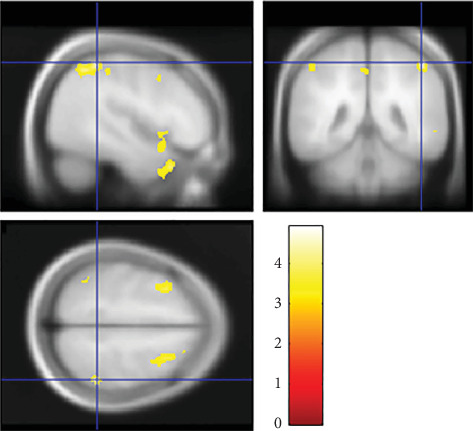

Previous research by Mehrinejad et al. found that parenting style affects offspring's brain development which later determines their creativity. They show that there is a significant positive relationship between authoritative parenting style and creativity. Meanwhile, neuroimaging studies by Takeuchi et al. have explained that offspring's creativity also differs depending on their empathizing-systemizing cognitive style. They show that both EQ and SQ were significantly and positively correlated with creativity. Combining the previous studies, we hypothesize that there exists an effect of the positive interaction between parenting style and the offspring's E-S cognitive style on the offspring's brain development and creativity. Whereas previous research on the offspring's creativity has focused on one dimension only, in the current study, for the first time, we investigated the effect of the interaction between parenting style and the offspring's E-S cognitive style on the offspring's brain development and creativity. We used voxel-based morphometry and questionnaires to investigate the gray matter correlates of the interaction between parenting style and the offspring's E-S cognitive style. With 675 healthy participants (average: 20 years old), using cross-sectional whole-brain multiple regression, we found significant interactive effects between parenting style and offspring's E-S cognitive style on regional gray matter volume (rGMV) in the right supramarginal gyrus (R-SMG). We also found that the rGMV in the R-SMG was significantly and positively correlated with the offspring's originality/fluency scores, a dimension of creativity. Our findings suggest that offsprings who are raised with the appropriate parenting style according to their E-S cognitive style have a larger rGMV in the R-SMG. These offsprings exhibit a higher level of creativity, especially originality in divergent thinking, the ability to generate an idea that is different from that of others. In the future, we hope this research can provide critical information for parents regarding the parenting style that suits their offspring's E-S cognitive style to improve offspring's creativity and quality of life.